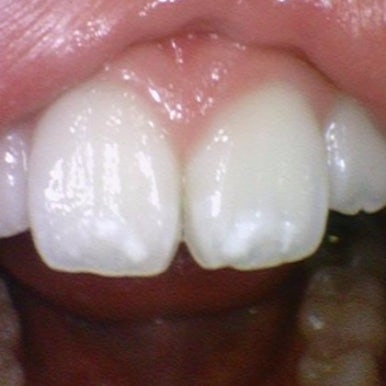

- 앞니 화이트 스팟 치료

화이트스팟, 반점치 전후 사진